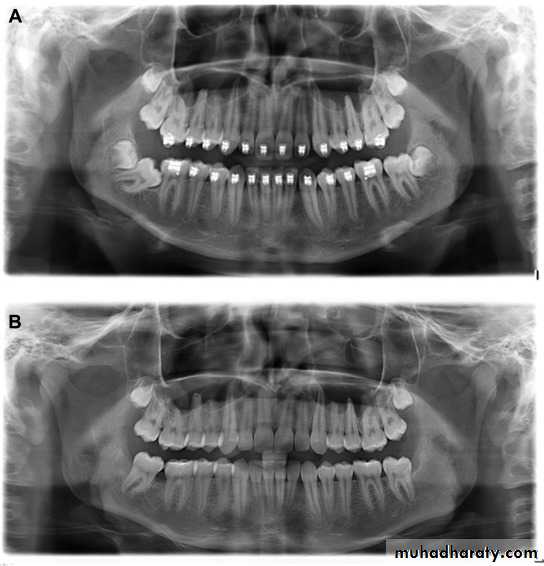

These are more in the males than in the females, they can be present in the primary dentition as well as in the permanent dentition, They are associated with cleidocranial dysostosis and cleft lip and palate.Supernumerary teeth can be classified according to their position into Mesiodens, Paramolar and Distomolar. According to the shape they can be conical (peg-shaped), supplementary; which have the shape and size of a normal tooth or they can have conventional shape with smaller or larger size.

Supernumerary teeth can have no effect on other standing teeth or they can cause failure of eruption of the other teeth, crowding, malposition or misalignment, resorption of the roots of the adjacent teeth or they can be associated with other pathologies (e.g. cysts).

Erupted supernumerary teeth are extracted easily especially if they are conical in shape. Unerupted teeth can be left in situ if they have no effect on the adjacent teeth but they should be monitored regularly. If they need removal they should be localized accurately using periapical films (buccal object rule may be applied) or vertex occlusal view. OPG is needed to determine the vertical position of the tooth and its position in relation with the floor of the nasal cavity or maxillary sinus.

They are approached palatally through palatal flap or buccally, bone removal and tooth sectioning may be needed, sometimes combined palatal and buccal approach is necessary.

It is essential to avoid damaging the roots of the adjacent teeth.